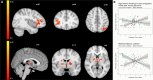

While impaired response inhibition has been reported in attention-deficit/hyperactivity disorder (ADHD), findings in disruptive behavior disorders (DBDs) have been inconsistent, probably due to unaccounted effects of co-occurring ADHD in DBD. This study investigated the associations of behavioral and neural correlates of response inhibition with DBD and ADHD symptom severity, covarying for each other in a dimensional approach. Functional magnetic resonance imaging data were available for 35 children and adolescents with DBDs (8-18 years old, 19 males), and 31 age-matched unaffected controls (18 males) while performing a performance-adjusted stop-signal task. No significant association was found between behavioral performance and symptom severities. However, contrasting successful inhibition with failed inhibition revealed that DBD and ADHD symptom severity was associated with greater activation in the right inferior frontal regions and reduced activation in the bilateral striatal regions, respectively. During successful inhibition versus go-trials, ADHD symptom severity was associated with the left lateral occipital cortex activation. The contrast of failed inhibition versus go-trials revealed reduced activation in the right frontal and left parietal regions associated with DBD symptom severity while ADHD symptom severity was associated with bilateral precunei, dorsolateral prefrontal and left posterior parietal regions. Except for the right inferior frontal regions during successful versus failed inhibition, all clusters were also found to be inversely associated with the other dimension of interest (i.e., DBD or ADHD symptoms). Opposite direction of the associations between DBD and ADHD symptom severity, and fronto-parietal and fronto-striatal activation suggest unique contributions of DBD and ADHD to the neural correlates of response inhibition.